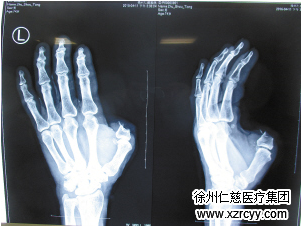

送到医院之后,betway在线登陆黎医生医生对王老汉进行了详细的诊断,判断是左手拇指近节指骨头体部及远节指骨缺。经过医护人员的努力,手术成功,王老汉的拇指被成功接上,现在已经在进行进一步的治疗。

左手拇指被锯掉